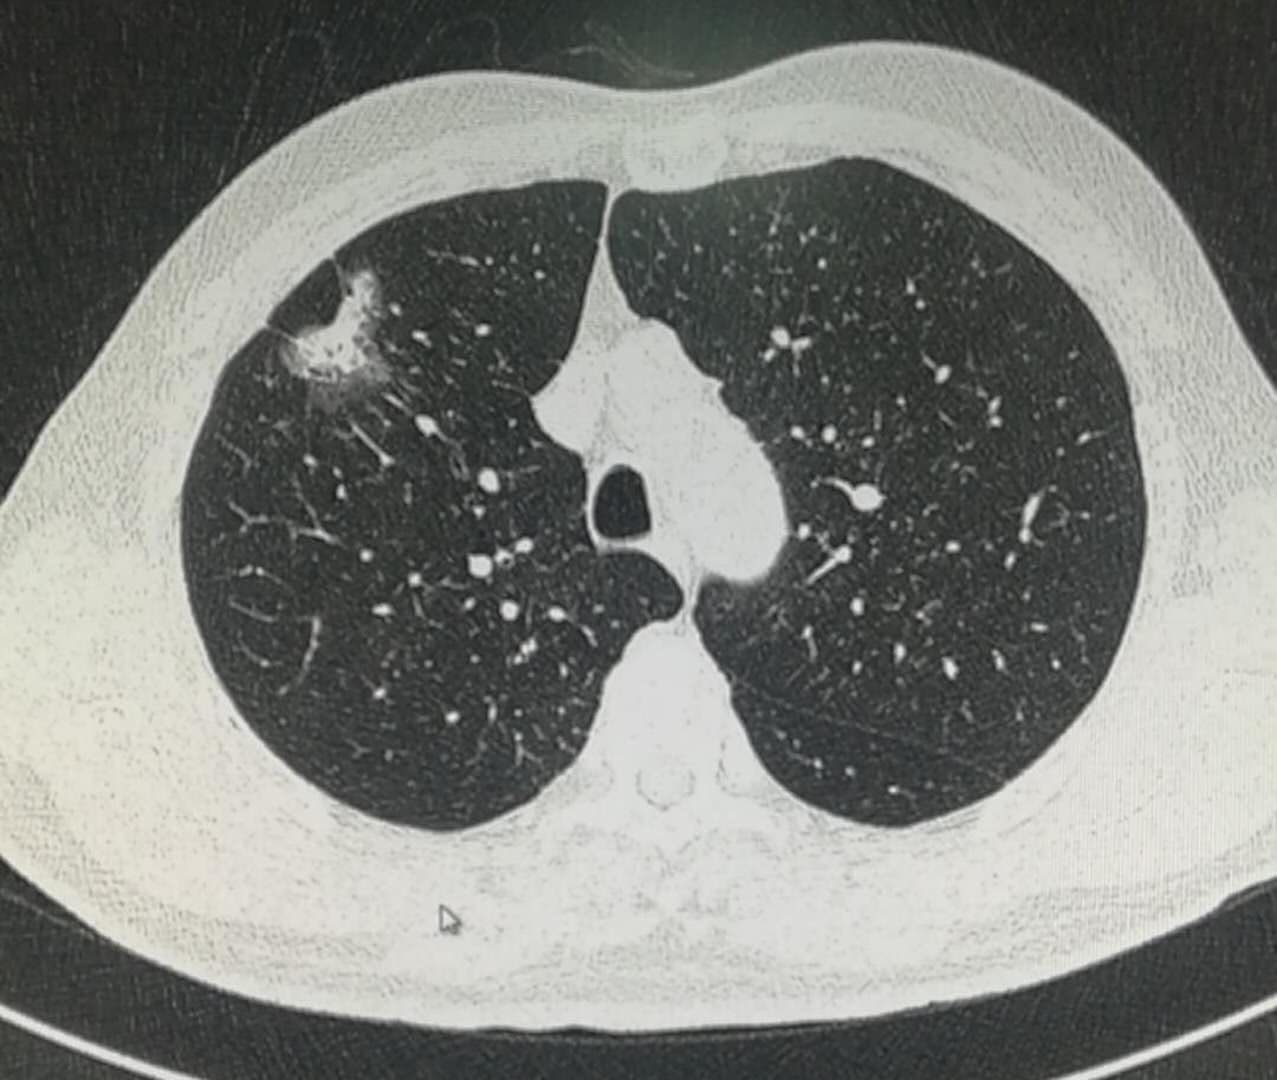

老爷子身板硬朗,没有任何不适症状,但是肺部CT发现了磨玻璃结节:

这个病灶位于右上肺叶,边界清晰,在磨纱玻璃密度内部还可以看到白色的实性密度区,所以属于混合磨玻璃密度结节;

同时还可以看到线样的胸膜牵拉: